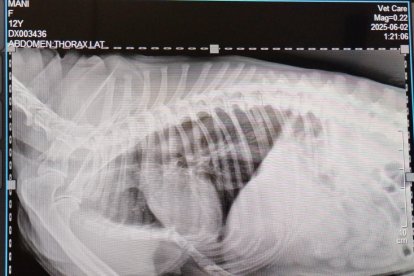

Le humectan los ojos con goteros que tienen componentes analgésico, le practican infusiones anestésicas para calmar de alguna forma el sufrimiento que siente. Tiene los pulmones dañados por la inhalación de humo y sus fosas nasales sangran por la inflamación. Se le dificulta respirar y se queja cuando lo hace. Por si fuera poco, luego de hacerle una radiografía se determinó que la perrita geriátrica tiene fracturas en las costillas y el esternón.